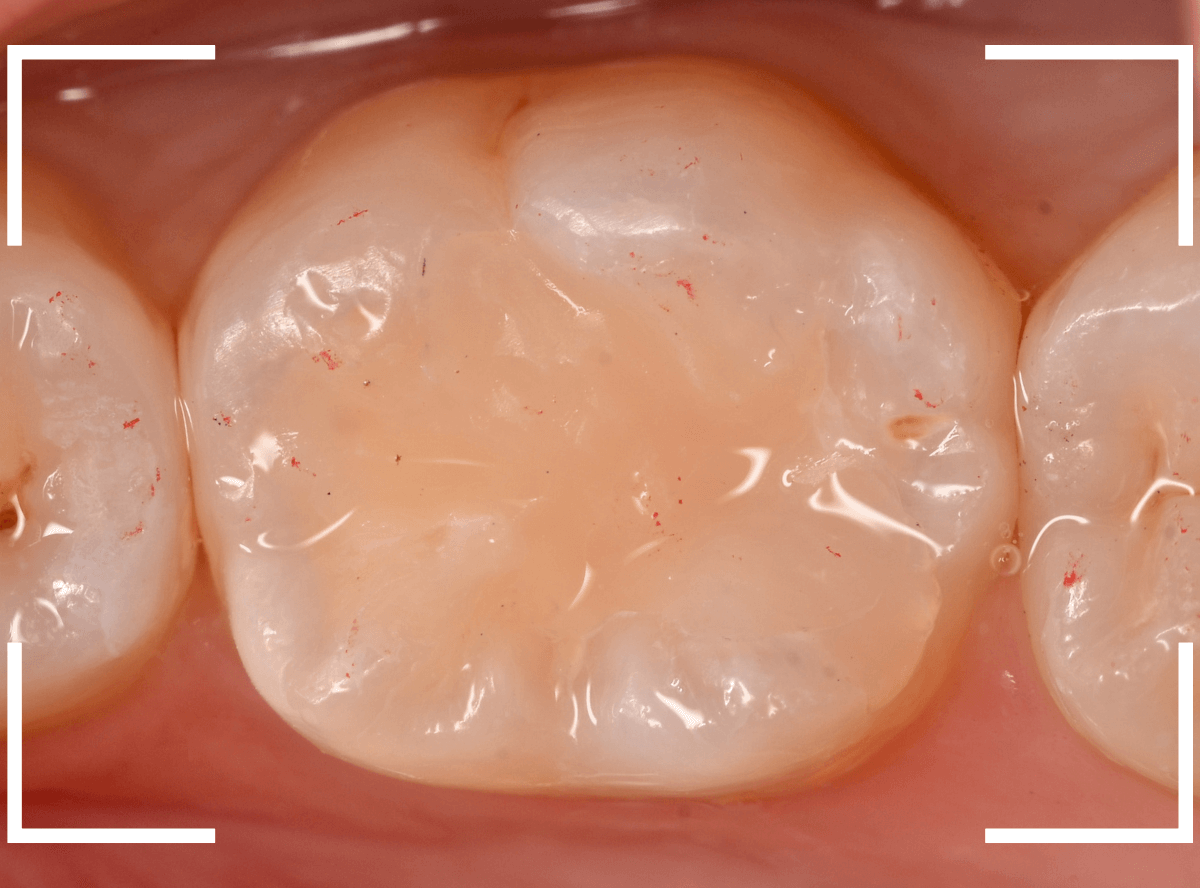

Case.7 レントゲンに写らないレジンの中の虫歯を削って調べる

こちらも定期検診希望で来院された患者さんです。

特に症状はありませんが、歯の咬頭(噛み合わせの山の部分)に小さな穴が空いていて、その周りがもやっと黒く見え、虫歯が怪しいです。

レントゲン写真で確認しますが、ここでは特に問題はなさそうに見えます。

患者さんに状況を説明し、慎重に削って調べる事になりました。

少しずつ穴の部分を削ってみると、ズブッと落とし穴にはまるような柔らかい虫歯の層(=軟化象牙質)に当たりました。

慎重に虫歯を除去したところです。

歯の溝のレジンが詰めてあった部分まで虫歯は進行していました。

とはいえ、それほど深く虫歯は進行していませんでしたので、虫歯除去後、レジンを充填して治療は終われました。

このように定期的にメンテナンスに来ていただくと虫歯が本格的に進行する前に対処する事ができます。